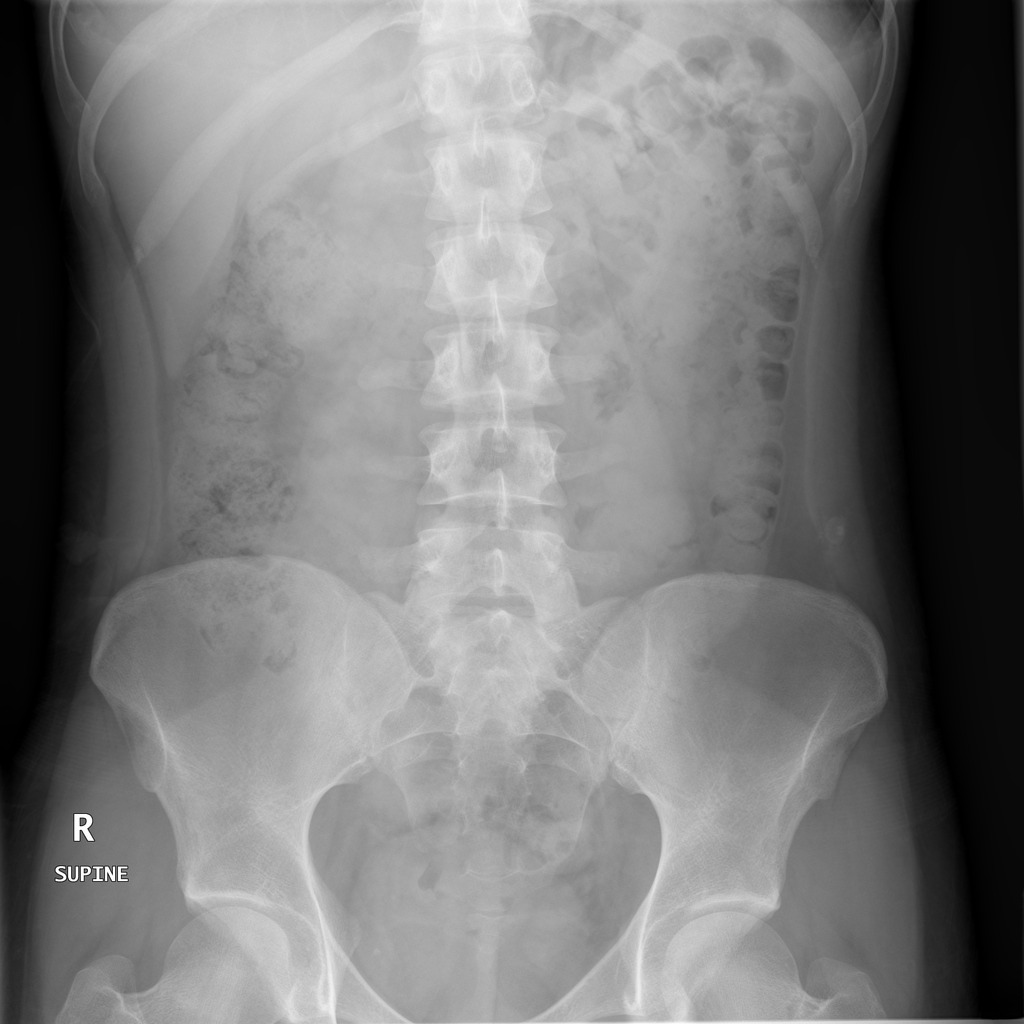

AXR showing pneumoperitoneum

air under diaphragm caused by perforation or surgery

normal axr

small bowel is central and have valvulae conniventes - lines crossing full width of bowel

Large bowel is more peripheral, mottled appearance due to faeces and gas content, haustra that do not cross whole width

Small bowel obstruction

valvulae conniventes confirm it’s small bowel

Large bowel obstruction

Coffee bean sign - sigmoid volvulus

twisted on mesentey in LIF

proximal bowel also dilated